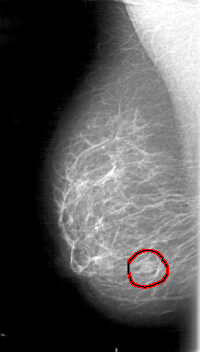

FILE: D_4071_1.RIGHT_CC.OVERLAY

TOTAL_ABNORMALITIES 1

ABNORMALITY 1

LESION_TYPE MASS SHAPE LOBULATED MARGINS OBSCURED

ASSESSMENT 0

SUBTLETY 2

PATHOLOGY BENIGN

TOTAL_OUTLINES 1

BOUNDARY